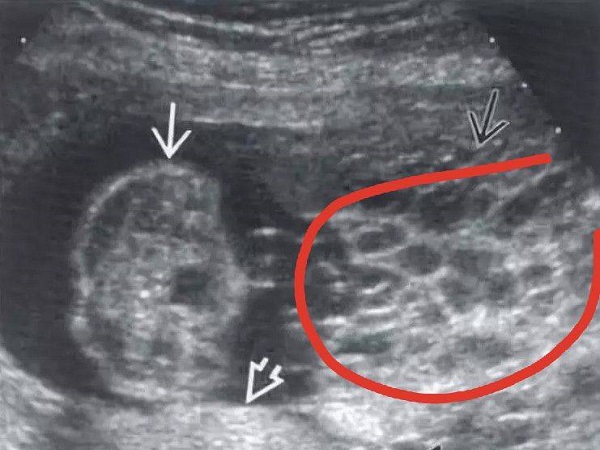

畸形胎儿比例上升 在哪些情况下会导致胎儿畸形

自从咱们的女性朋友打算要孩子的时候开始,咱们的就一再强调,希望咱们的备孕女性朋友和孕妈妈都能过改掉自己身上不利于胎儿生长或者容易致胎儿畸形的坏习惯。但是,还是要..